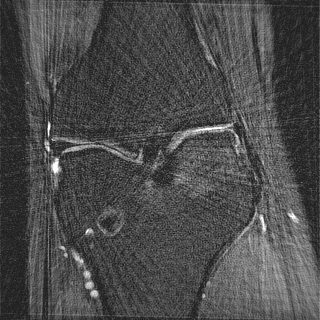

This article presents a novel undersampled magnetic resonance imaging (MRI) technique that leverages the concept of Neural Radiance Field (NeRF). With radial undersampling, the corresponding imaging problem can be reformulated into an image modeling task from sparse-view rendered data; therefore, a high dimensional MR image is obtainable from undersampled $k$-space data by taking advantage of implicit neural representation. A multi-layer perceptron, which is designed to output an image intensity from a spatial coordinate, learns the MR physics-driven rendering relation between given measurement data and desired image. Effective undersampling strategies for high-quality neural representation are investigated. The proposed method serves two benefits: (i) The learning is based fully on single undersampled $k$-space data, not a bunch of measured data and target image sets. It can be used potentially for diagnostic MR imaging, such as fetal MRI, where data acquisition is relatively rare or limited against diversity of clinical images while undersampled reconstruction is highly demanded. (ii) A reconstructed MR image is a scan-specific representation highly adaptive to the given $k$-space measurement. Numerous experiments validate the feasibility and capability of the proposed approach.